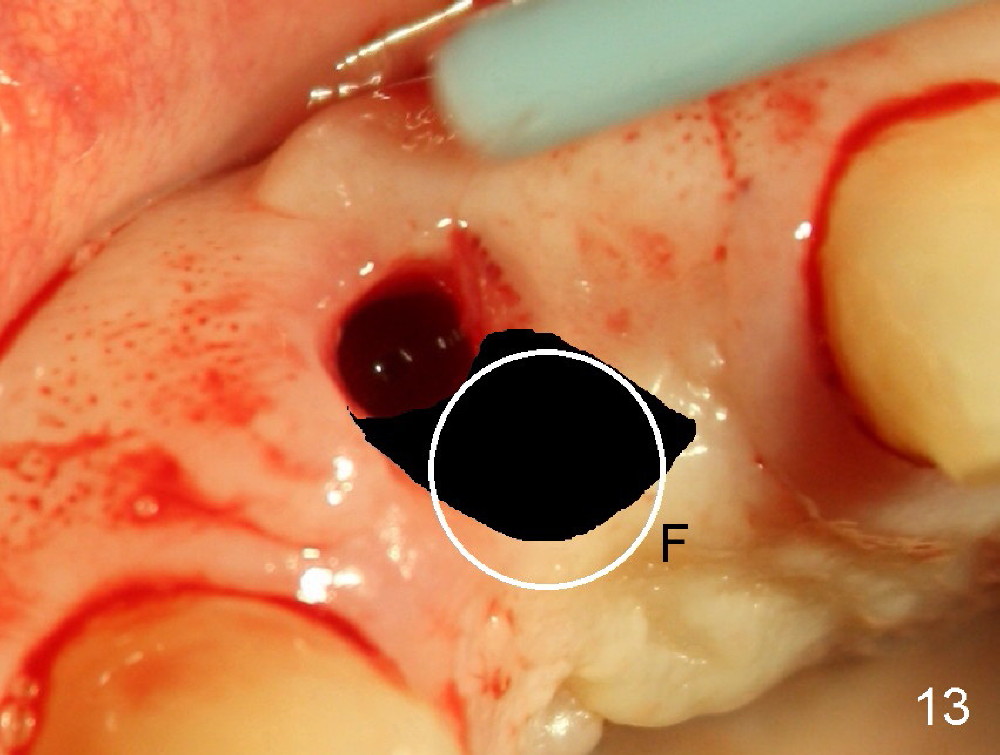

Malpositioned implant in the anterior region is cosmetically unacceptable. Immediate provisional allows us to note the issue immediately. The crown looks too long. Secondly, the provisional is easily dislodged, since the buccal aspect of the angled abutment is over trimmed (Fig.1). The implant (3.8x14 mm), which has been placed 3.5 months, is unexpectedly easily removed by reverse torque (Fig.2). The buccal wall is intact, whereas there seems to be enough bone lingually to place an implant. A small incision is made (Fig.11) so that the gingival tissue can be transferred buccally (Fig.12) and the immediate implant is to be placed palatally (Fig.13 white circle). There is no difficulty forming osteotomy in the palatal wall, followed by inserting 4.5x20 mm tap at the depth of 17 mm (Fig.3,5). But the tap is not palatal enough (Fig.4). By removing more palatal bone, the 4.5x17 implant (Fig.6) appears to be placed palatally enough for restoration (Fig.7; A: abutment; *: buccal gap). The biggest problem is that the palatal flap (Fig.7 arrowheads) cannot be pushed buccally; instead remains palatally. This leads to buccal tissue deficiency (Fig.8). Connective tissue graft is offered, but declined. The patient insists that she has low smile line. Following immediate provisional, mixture of allograft and synthetic graft is placed in the buccal gap (Fig.9). The overbuilt graft is held in place by perio dressing.